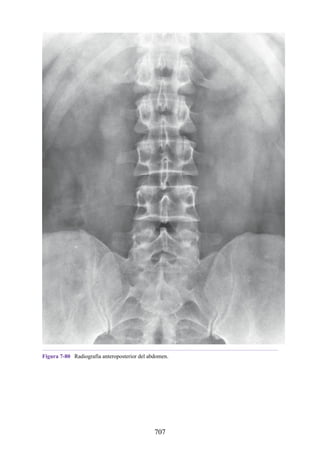

Notas clínicas

Lesiones ligamentosas